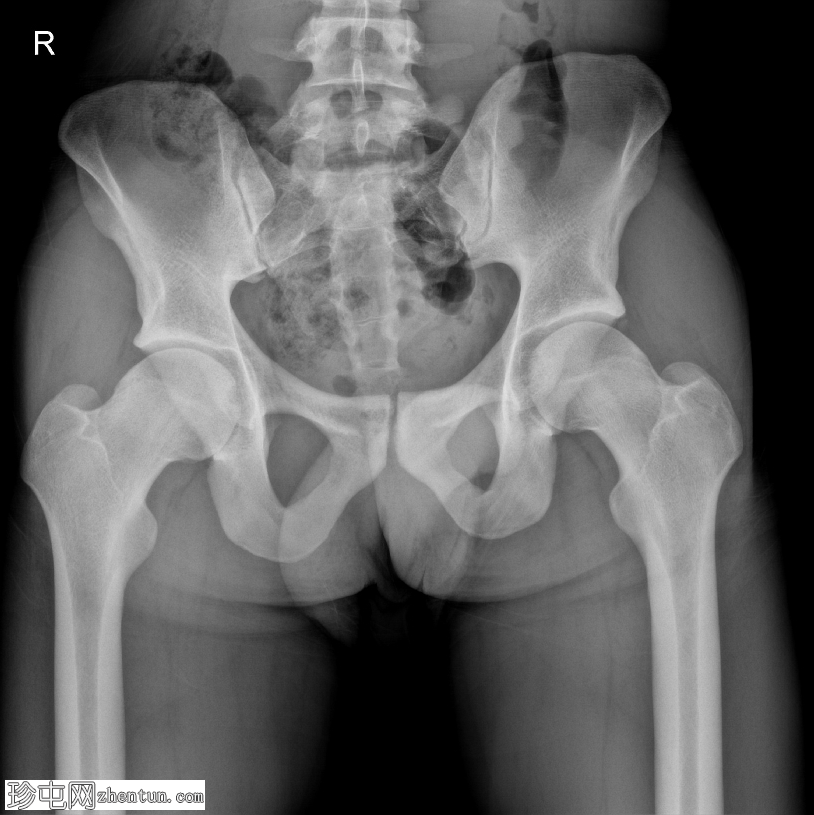

双侧髋关节排列正常,关节间隙保持良好,无急性骨折或脱位征象。左侧髋臼上外侧缘可见一小块皮质良好的听小骨,与髋臼骨相符,系偶然发现。

股骨头颈交界处双侧正常凹陷消失,形成手枪式握把轮廓,右侧更为明显。骶髂关节和耻骨联合外观完整,无明显退行性病变或软组织异常。